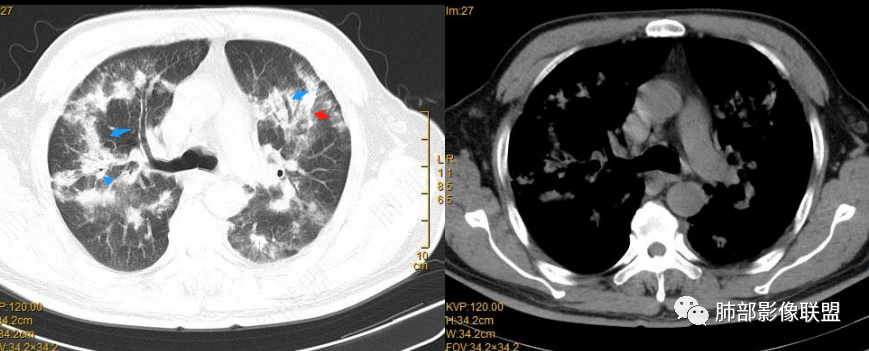

宇宙: 两肺沿支气管血管束及胸膜下分布多发结节、斑片及实变,边缘模糊,右肺病灶可见反晕,复查吸收好转,边界清,考虑OP

良孑: 两肺多发实变及结块,沿支气管血管束分布,可见反晕征,考虑显微镜下多血管炎或0P

peek_knight: 双肺弥漫分别斑片影和结节影,沿支气管分布,见反晕征,考虑OP

2022.2.17CT显示两肺中内带多发结节影、斑片影、条索影,部分病灶侧向融合与胸膜平行。部分病灶沿着支气管血管束分布、其内支气管稍扩张。部分病灶呈反晕征。大部分病灶边界显示清晰,部分病灶周围可见边界不清的GGO。2022.4.12CT显示两肺中内带多发结节影、条索状、条带状高密度影,边界收缩平直凹陷,大部分病灶沿着支气管血管束分布,亦有位于胸膜下侧向融合与胸膜平行的病灶。总体与第一次CT对比两肺病灶明显吸收。